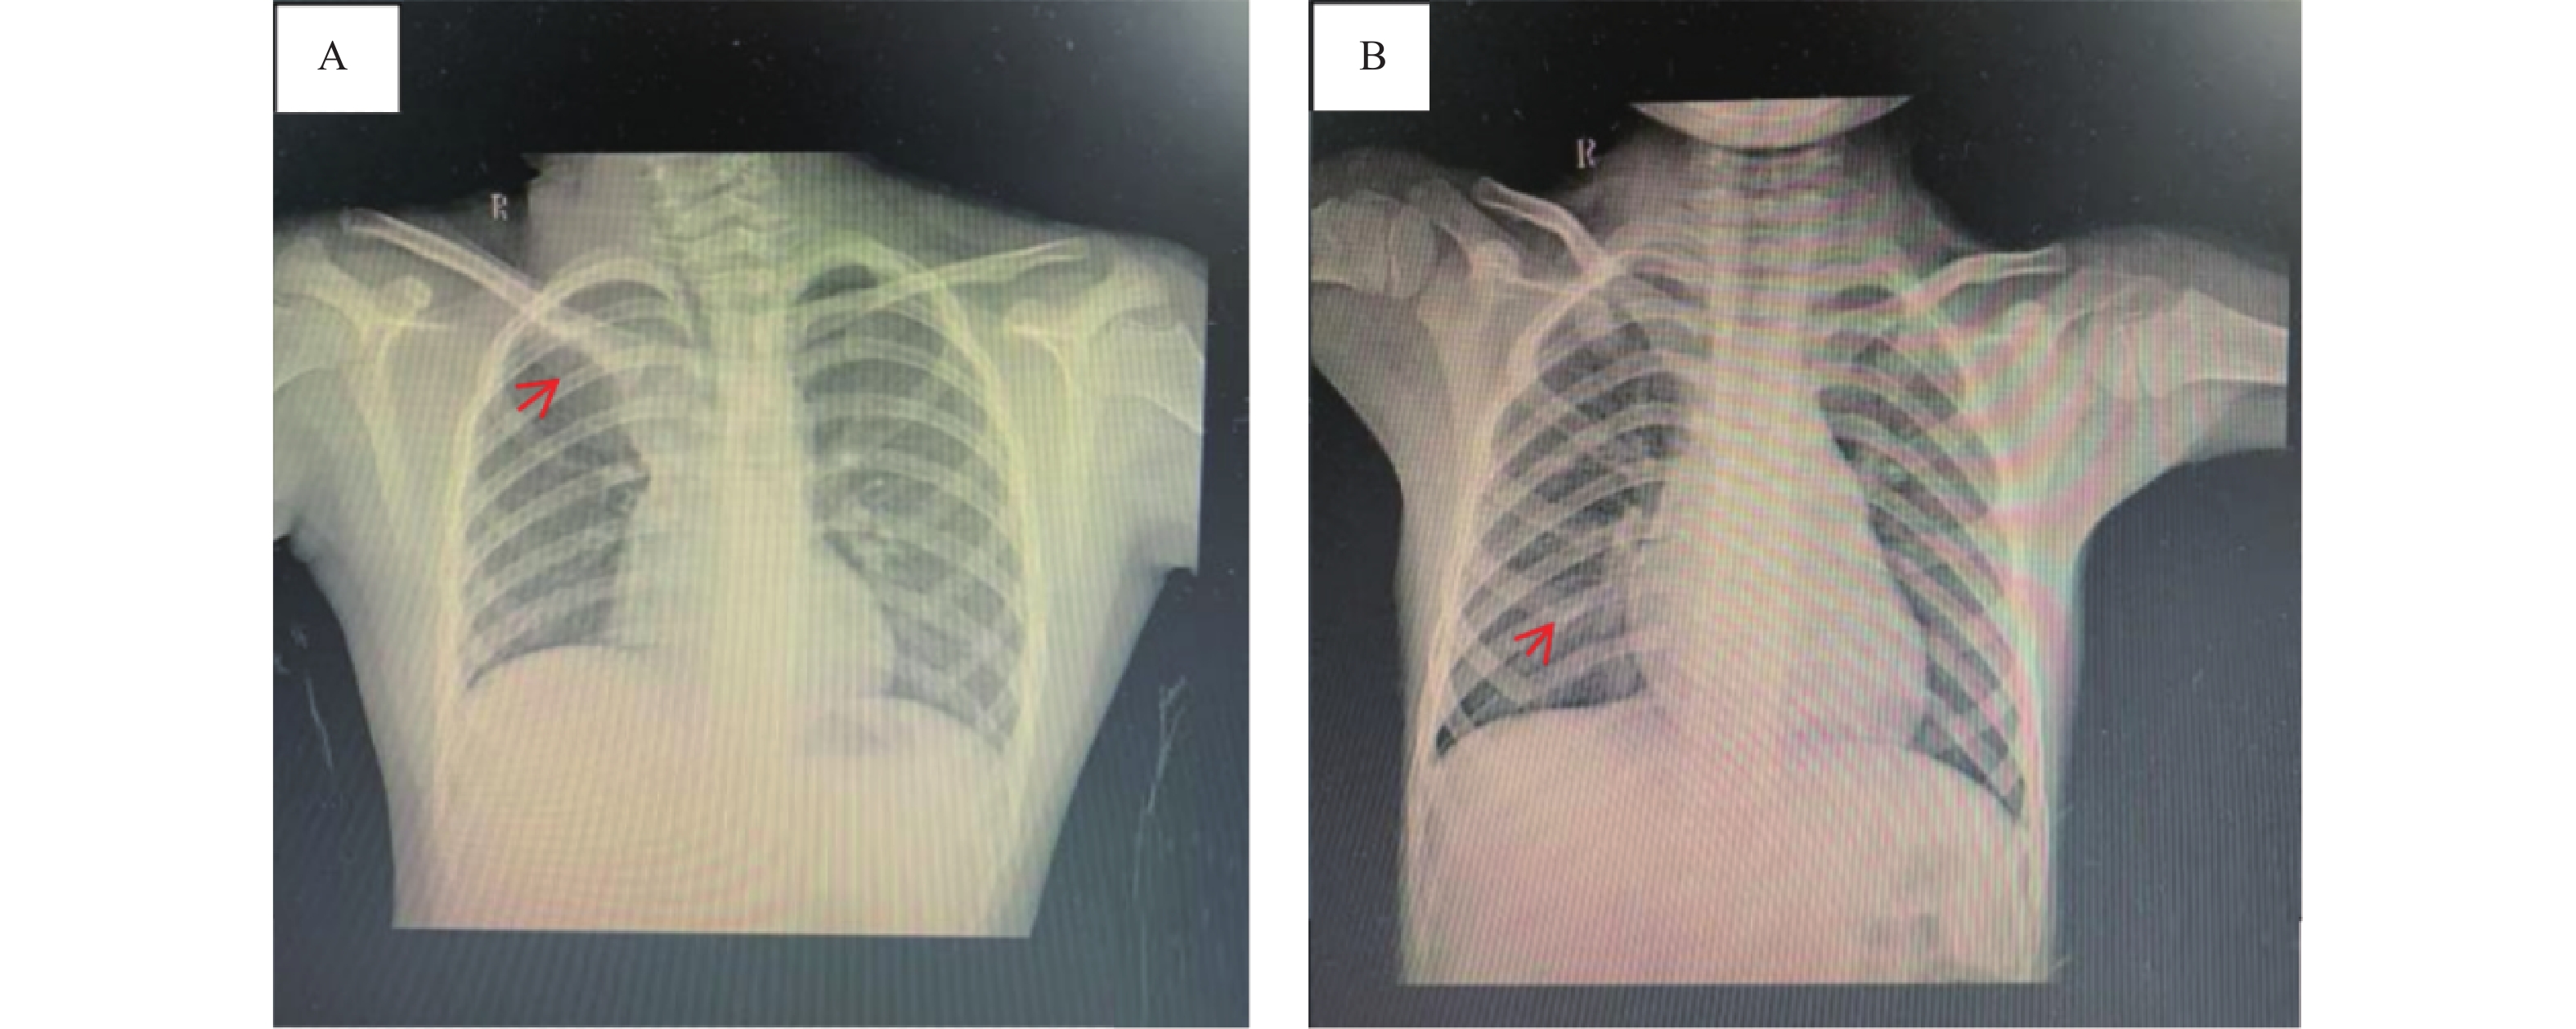

不同红细胞压积水平非小细胞肺癌伴胸腔积液患者临床病理特征及其与预后的相关性

江汝伟, 徐丽君, 王惠茹, 黄思宇

摘要(104) HTML(62) PDF (34)

摘要:

目的  探讨非小细胞肺癌(non-small cell lung cancer,NSCLC)伴胸腔积液(pleural effusion,PE)患者红细胞压积(hematocrit,HCT)水平的临床影响因素,并深入分析HCT水平对患者预后的影响。  方法  选取2020年1月至2025年5月期间于安徽省颍上县人民医院确诊治疗的NSCLC伴PE患者125例,根据患者治疗4周期后HCT水平,按三分位数将其分为高HCT组(>39.84%,n = 41)、中HCT组(36.52%~39.84%,n = 43)和低HCT组(<36.52%,n = 41)。采用逐步校正回归分析探讨临床病理特征与治疗4周期后HCT水平的关系;多因素Logistic回归对治疗4周期后HCT水平与预后不良的独立相关性进行分析;E值法进行敏感性分析;亚组分析不同血常规指标、癌胚抗原(carcinoembryonic antigen,CEA)、细胞核相关抗原67(Ki67 nuclear-associated antigen,Ki67)水平下,治疗4周期后HCT水平与NSCLC伴PE患者预后的关系;区间似然比分析治疗4周期后不同HCT水平的预后不良情况;受试者工作特征曲线(receiver operating characteristic,ROC)并计算曲线下面积(area under curve,AUC)分析治疗4周期后不同HCT水平对预后不良的预测;限制性立方样条(restricted cubic spline,RCS)分析治疗4周期后不同HCT水平与预后不良的剂量-反应关系;Kaplan-Meier生存曲线分析治疗4周期后不同HCT水平对预后不良的影响。  结果  三组患者的性别、年龄、淋巴结转移、分化程度、肿瘤分期、吸烟史、HCT、淋巴细胞(lymphocyte,LY)计数、中性粒细胞(neutrophilic granulocyte,NE)计数、中性粒细胞淋巴细胞计数比值(neutrophil-lymphocyte ratio,NLR)、嗜酸粒细胞(eosinophils,EOS)计数、CEA、Ki67、血红蛋白(hemoglobin,Hb)、铁蛋白(ferritin,Fer)、转铁蛋白饱和度(transferrin saturation,TSAT)、白蛋白(albumin,ALB)、C反应蛋白(C-reactive protein,CRP)、客观缓解率、疾病控制率水平差异均有统计学意义(P < 0.05)。性别、吸烟史、肿瘤分期、淋巴转移与HCT水平密切相关(P < 0.05)。预后良好组治疗后HCT水平均明显高于预后不良组(P < 0.05)。校正混杂因素后,治疗4周期后HCT水平与预后不良的风险仍存在独立相关性(OR = 1.472,95%CI:1.345~1.620)。敏感性分析显示E值为3.983。亚组分析结果显示,在不同NE、LY、NLR、EOS、CEA、Ki67区间范围内,治疗4周期后HCT水平均与NSCLC伴PE患者预后相关。低HCT组阳性似然比为6.468,95%CI:2.703~15.478,P < 0.001,低HCT水平可明显增加预后不良的风险;高HCT组阳性似然比减小至0.064,95%CI:0.009~0.450,P < 0.05,高HCT水平可明显降低预后不良的风险。治疗4周期后HCT水平在总体、女性、男性患者群体内对预后不良均具有高等预测效能,其AUC分别为0.940(95%CI:0.733~0.988)、0.823(95%CI:0.767~0.876)、0.844(95%CI:0.753~0.903),得到HCT水平最佳截断值分别为36.24%、32.89%、35.35%。RCS结果显示总体、女性、男性患者群体治疗4周期后HCT水平与预后不良风险的关联强度均呈非线性剂量-反应关系(Pfor non linear<0.05)。Kaplan-Meier生存曲线结果显示,治疗4周期后中、高HCT水平患者的无进展生存期(progression-free survival,PFS)明显高于低HCT水平患者,差异具有统计学意义(P < 0.05)。  结论  低HCT水平可明显增加NSCLC伴PE患者预后不良的风险,当HCT≤36.24%时,HCT水平与预后不良风险的关联强度明显升高,且在不同NE、LY、NLR、EOS、CEA、Ki67水平下HCT水平均与预后相关。临床诊疗综合监测上述指标对于评估此类患者预后具有重要的临床价值。